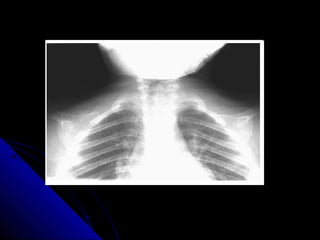

RRoottaattiioonn

RRoottaattiioonn ooff tthhee rraaddiiooggrraapphh iiss aasssseesssseedd bbyy

jjuuddggiinngg tthhee ppoossiittiioonn ooff tthhee ccllaavviiccllee hheeaaddss

aanndd tthhee tthhoorraacciicc ssppiinnoouuss pprroocceessss.. IIddeeaallllyy

tthhee ccllaavviiccllee hheeaaddss sshhoouulldd bbee eeqquuiiddiissttaanntt

ffrroomm tthhee ssppiinnoouuss pprroocceessss..

14 RRoottaattiioonn RRoottaattiioonnooff tthhee rraaddiiooggrraapphh iiss aasssseesssseedd bbyy jjuuddggiinngg tthhee ppoossiittiioonn ooff tthhee ccllaavviiccllee hheeaaddss aanndd tthhee tthhoorraacciicc ssppiinnoouuss pprroocceessss.. IIddeeaallllyy tthhee ccllaavviiccllee hheeaaddss sshhoouulldd bbee eeqquuiiddiissttaanntt ffrroomm tthhee ssppiinnoouuss pprroocceessss..